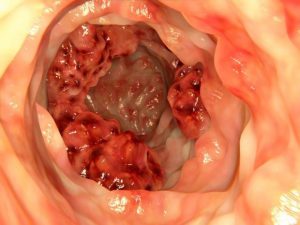

Por Estephania Baez Cancer-de-colon-visto-a-traves-de-clonoscopia-620x465

El cáncer de colon es una enfermedad en la que células malignas atacan la porción intermedia y más larga del intestino grueso. Las principales causas de este tipo de cáncer son hereditarias aunque otros factores son los hábitos poco saludables en cuanto a la alimentación. por esto, en los últimos años un nuevo estudio demostró que las nuevas tendencias alimenticias pueden ayudar a prevenir esta enfermedad.

El cáncer de colon es de los más peligrosos, ya que es asintomático en la etapa temprana, por lo que es más difícil de detectar en la primera fase.